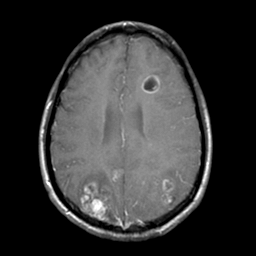

Sarcoma, MR Study #1 mr-gad -- Slice #16

[Home][Help][Clinical] Slice 16